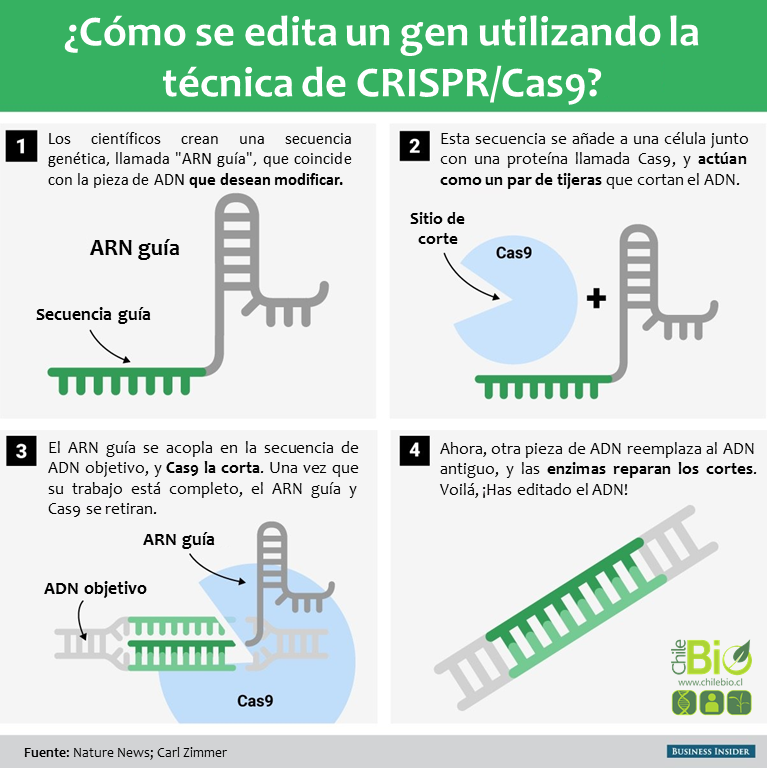

EL MIEDO MILENARIO

Algunas personas se asustan demasiado por el tipo de tecnología dirigida al